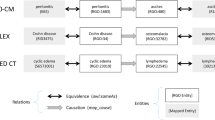

Radiology teaching file repositories contain a large amount of information about patient health and radiologist interpretation of medical findings. Although valuable for radiology education, the use of teaching file repositories has been hindered by the ability to perform advanced searches on these repositories given the unstructured format of the data and the sparseness of the different repositories. Our term coverage analysis of two major medical ontologies, Radiology Lexicon (RadLex) and Unified Medical Language System (UMLS) Systematized Nomenclature of Medicine Clinical Terms (SNOMED CT), and two teaching file repositories, Medical Imaging Resource Community (MIRC) and MyPacs, showed that both ontologies combined cover 56.3% of terms in the MIRC and only 17.9% of terms in MyPacs. Furthermore, the overlap between the two ontologies (i.e., terms included by both the RadLex and UMLS SNOMED CT) was a mere 5.6% for the MIRC and 2% for the RadLex. Clustering the content of the teaching file repositories showed that they focus on different diagnostic areas within radiology. The MIRC teaching file covers mostly pediatric cases; a few cases are female patients with heart-, chest-, and bone-related diseases. The MyPacs contains a range of different diseases with no focus on a particular disease category, gender, or age group. MyPacs also provides a wide variety of cases related to the neck, face, heart, chest, and breast. These findings provide valuable insights on what new cases should be added or how existent cases may be integrated to provide more comprehensive data repositories. Similarly, the low-term coverage by the ontologies shows the need to expand ontologies with new terminology such as new terms learned from these teaching file repositories and validated by experts. While our methodology to organize and index data using clustering approaches and medical ontologies is applied to teaching file repositories, it can be applied to any other medical clinical data.